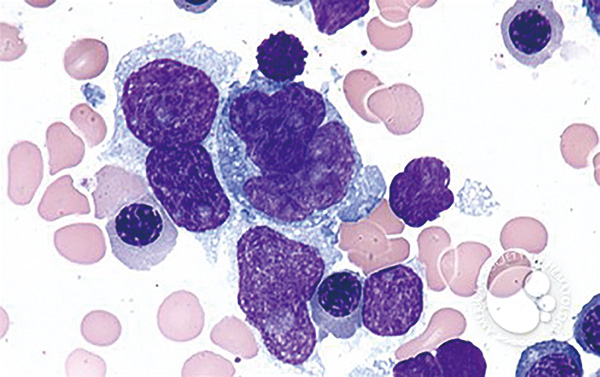

高危LBCL患者接受一线R-CHOP方案的治愈概率<50%,因此需要改善预后。由于筛查要求,疾病负荷大或快速进展的患者通常被排除在一线治疗的临床试验之外。

为了最大限度地缩短诊断和治疗之间的时间,该项研究者发起的Ⅱ期随机临床研究(COALITION)纳入≤65岁的、至少携带一项高危特征(国际预后指数IPI≥3、NCCN-IPI≥4,或MYC和BCL2和/或BCL6重排)的、接受一个周期R-CHOP治疗的此类患者,分予5个周期的Glofit-Pola-R-CHP(40例)或Glofit-R-CHOP(40例),然后给予2个周期的格菲妥单抗巩固治疗。